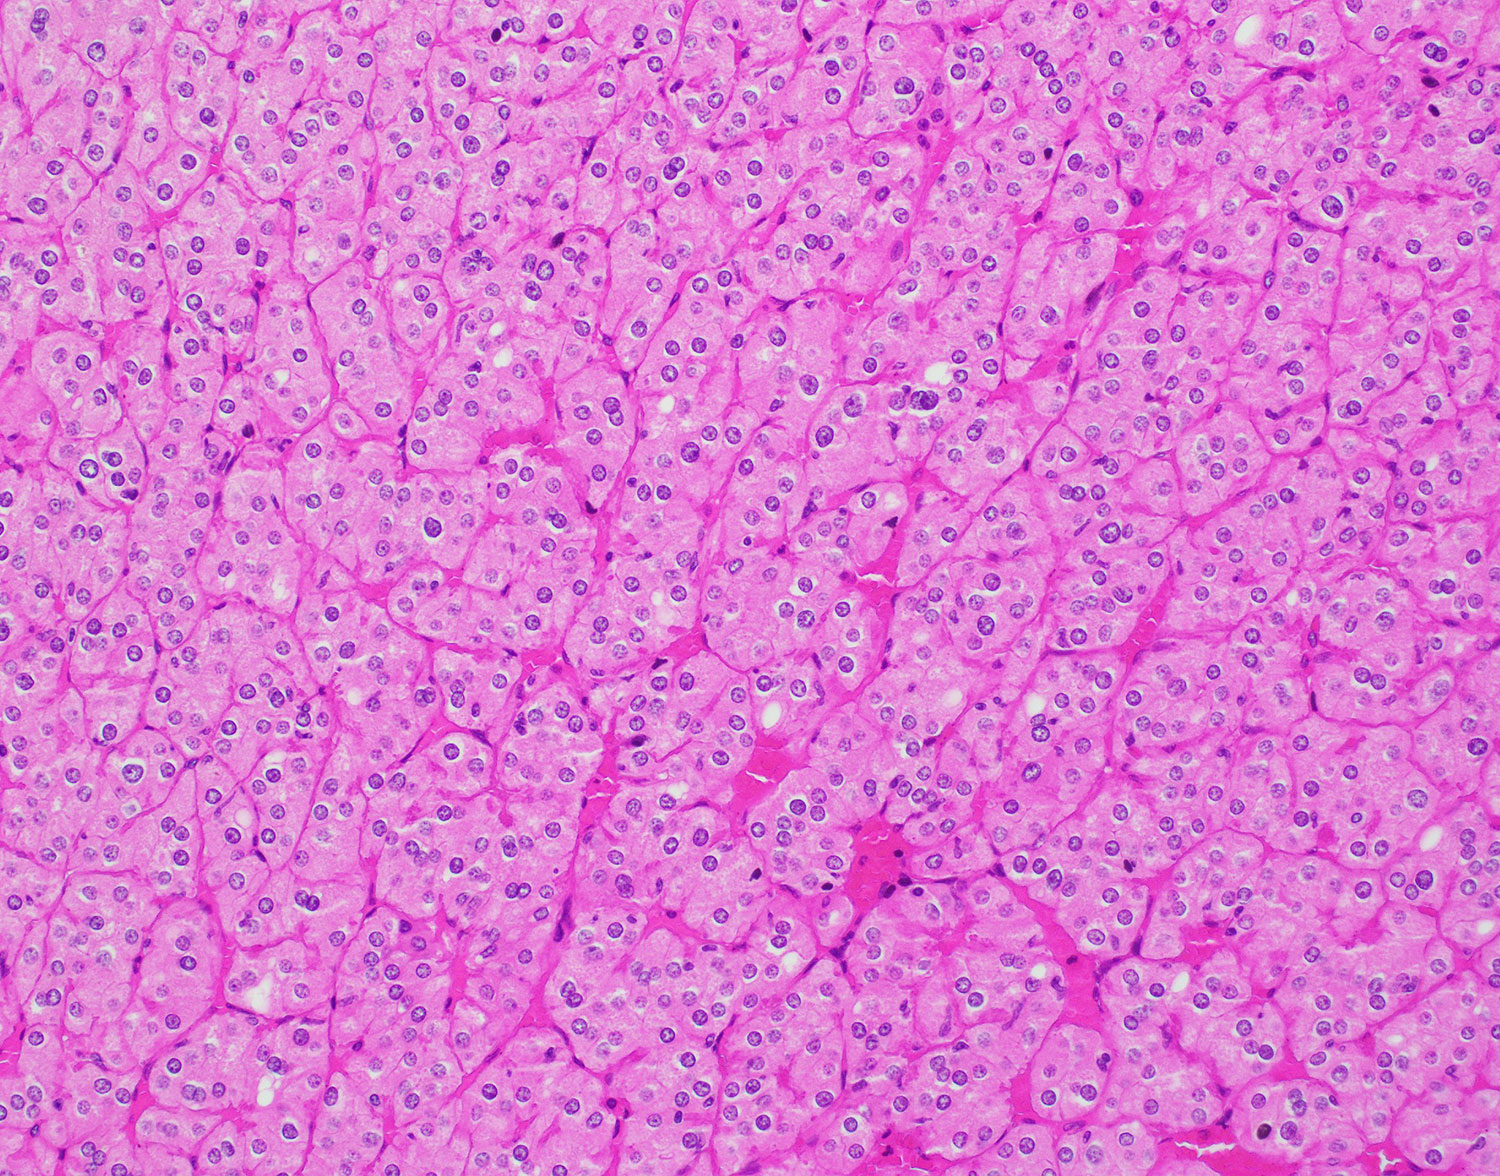

Gross examination of the nephrectomy specimens revealed that the parenchyma of the bilateral kidneys was entirely replaced by innumerable thin-walled cysts. One of the cysts within the right kidney had a calcified and slightly thickened wall.